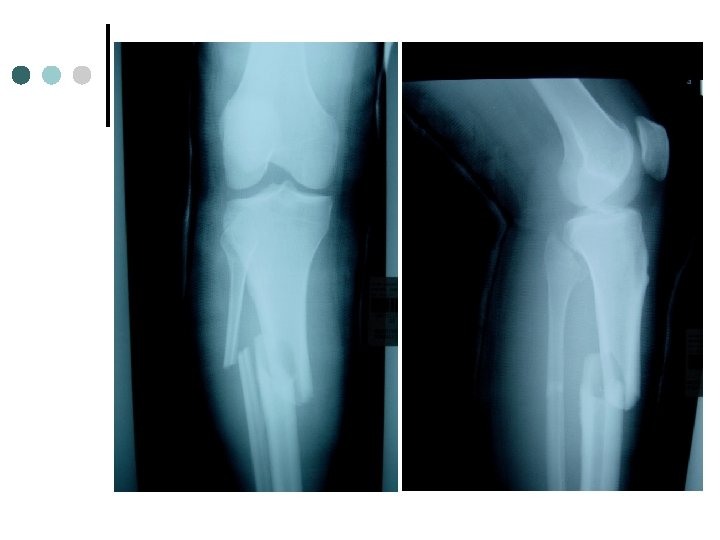

Tibia/Fibula Fractures Cause: Direct Force, rotary force ¢ S/S: Immediate pain, swelling, possible deformity ¢ TX: Immediate referral to MD ¢ Prevention: Wear proper shin protection ¢